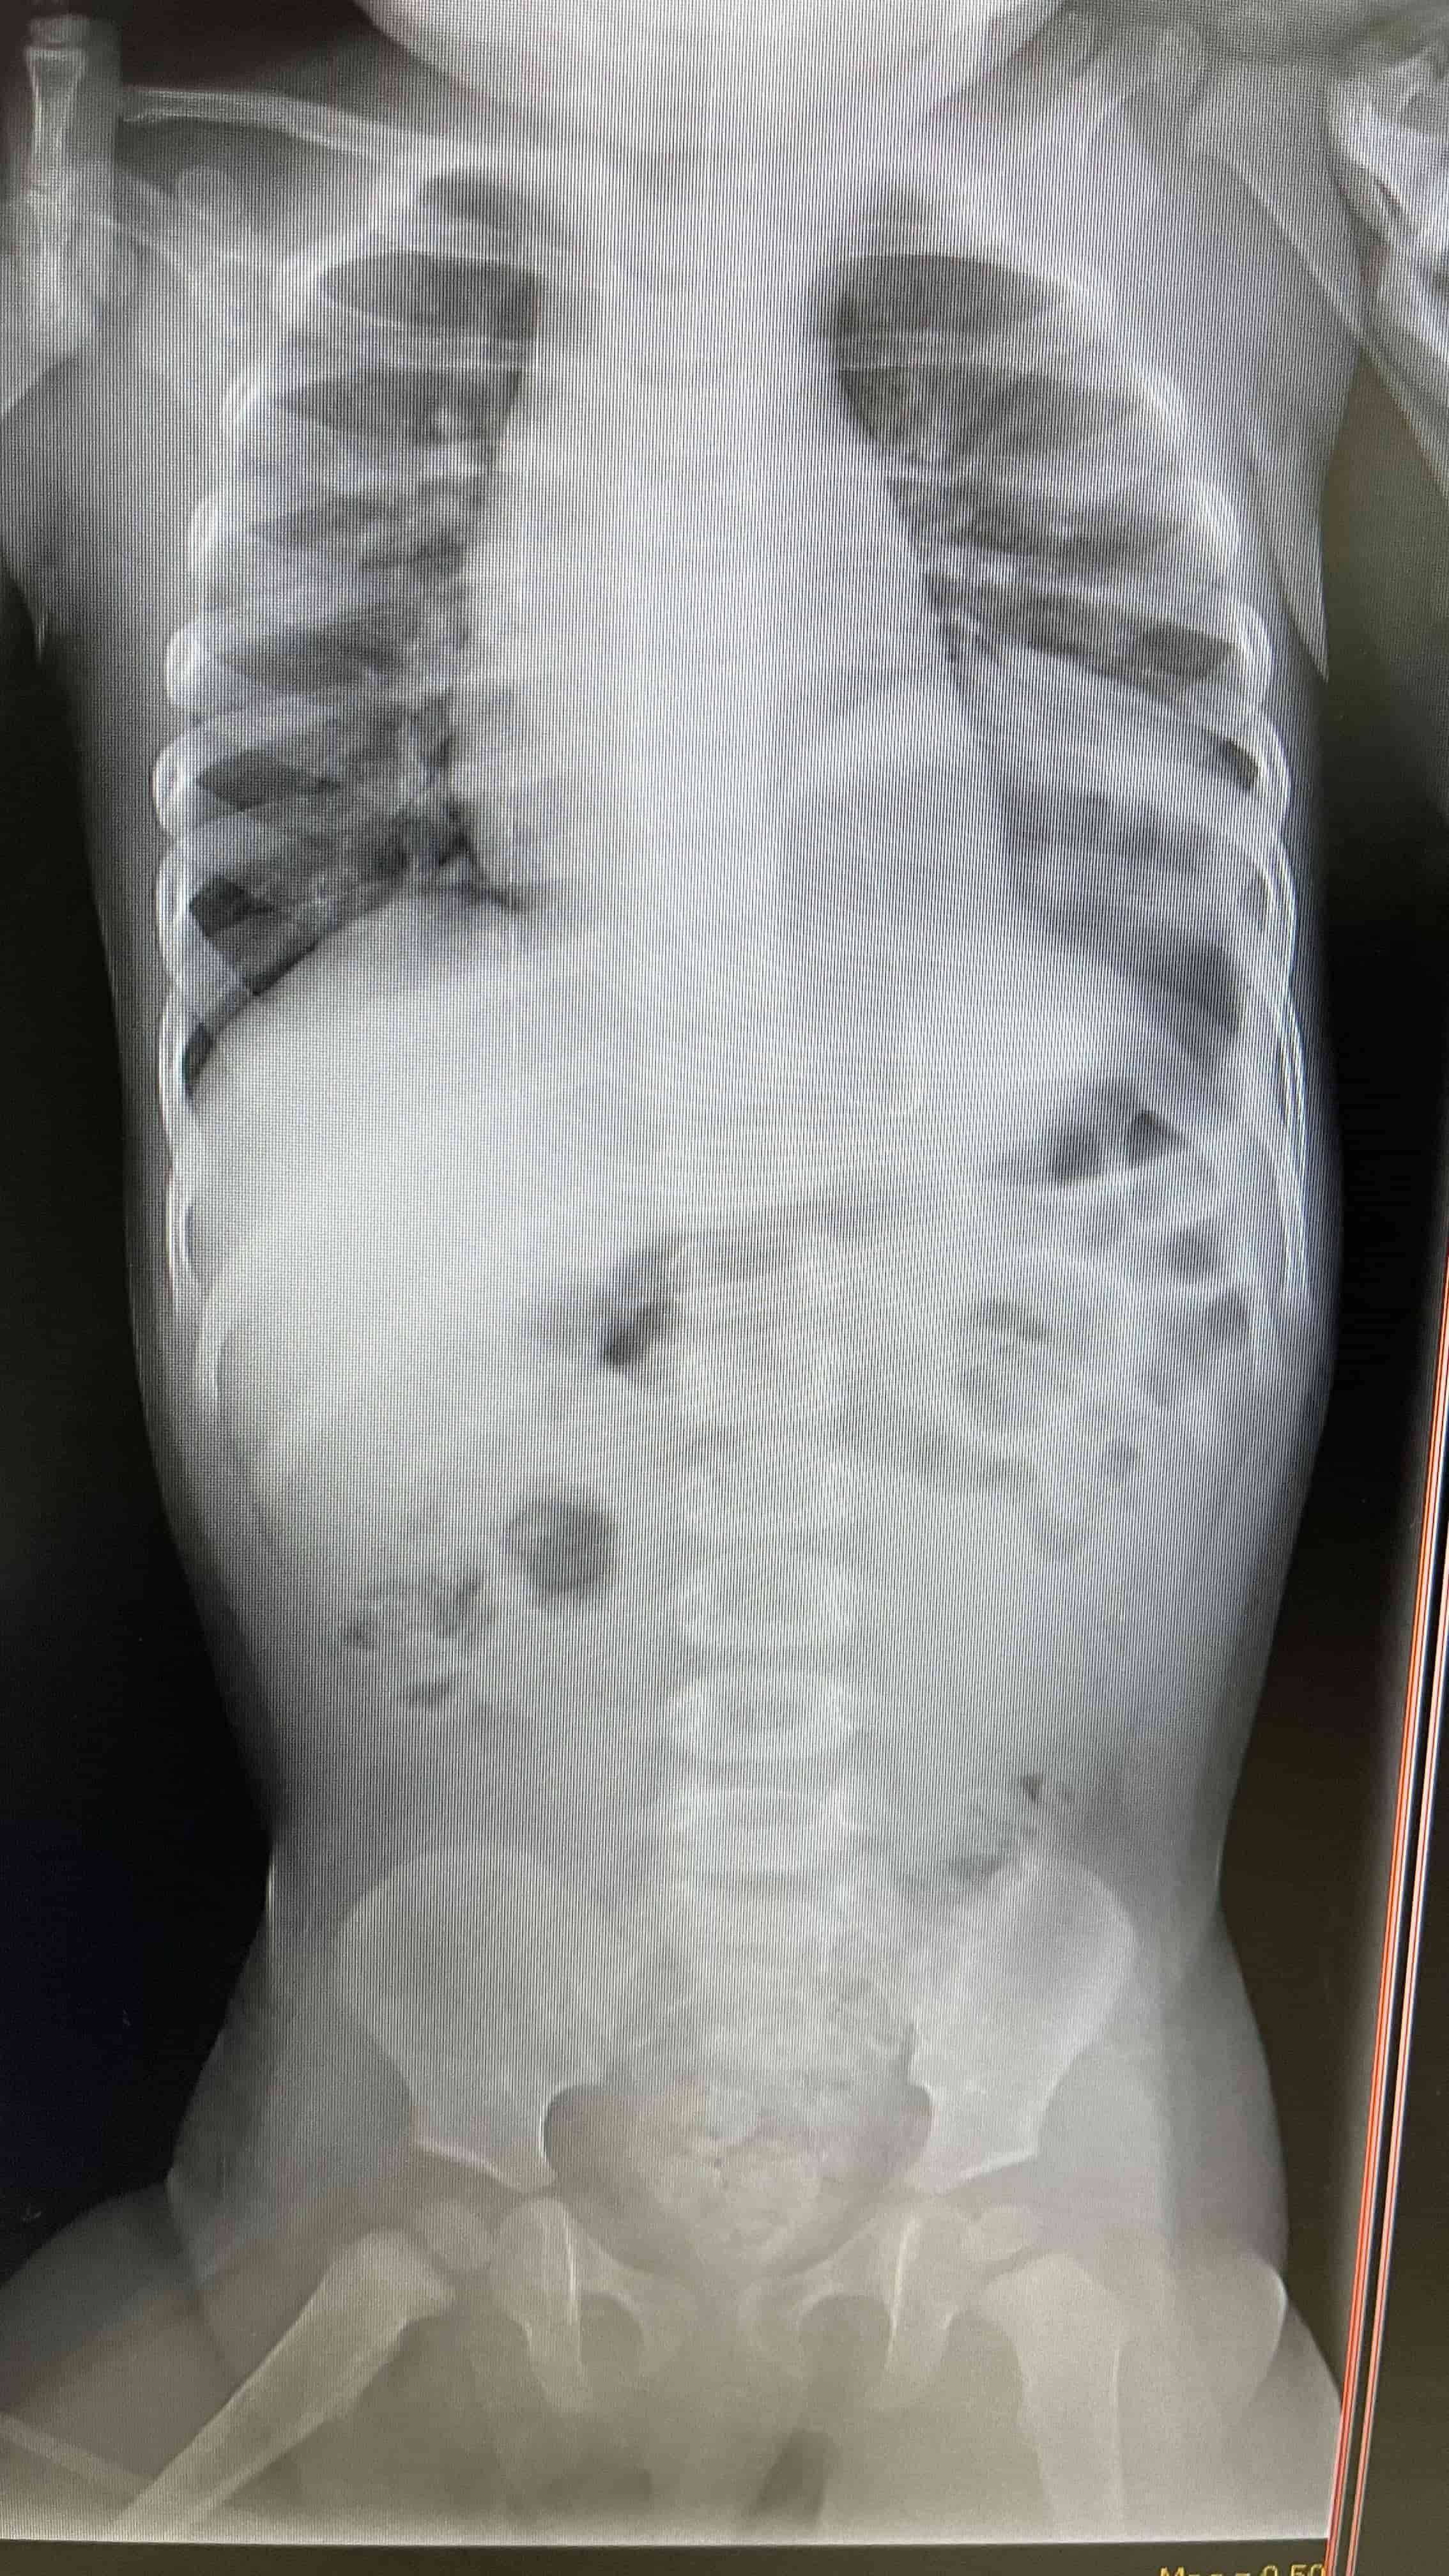

"Se drenó bastante contenido estomacal y aire, e inmediatamente la niña comenzó a recuperar e interactuar. La niña se recuperó completamente luego de una cirugía en donde se reparó el diafragma. Si no hubiéramos actuado rápido, este panorama alentador no lo hubiéramos tenido. Debido a que el estómago estaba empujando el mediastino, esto hace que la cantidad de sangre que llega al corazón sea mínima, lo que repercute en la circulación de la misma en tejidos periféricos y su actividad no es la misma que una persona normal", detalló por su parte el Dr. Falcón.

Médicos salvan la vida de infante con hernia diafragmática y gastrotórax a tensión  Placa lateral portable, se demuestra la hernia diafragmática. Médicos salvan la vida de infante con hernia diafragmática y gastrotórax a tensión  Radiografía de pecho y abdomen, luego de tratamiento con tubonasogástrico. Se demuestra mejoría marcada en desplazamiento deestructuras mediastinales. Médicos salvan la vida de infante con hernia diafragmática y gastrotórax a tensión  Placa de pecho portable luego de reparación quirúrgica del diafragma.

Médicos salvan la vida de infante con hernia diafragmática y gastrotórax a tensión  Placa de pecho portable luego de reparación quirúrgica del diafragma.